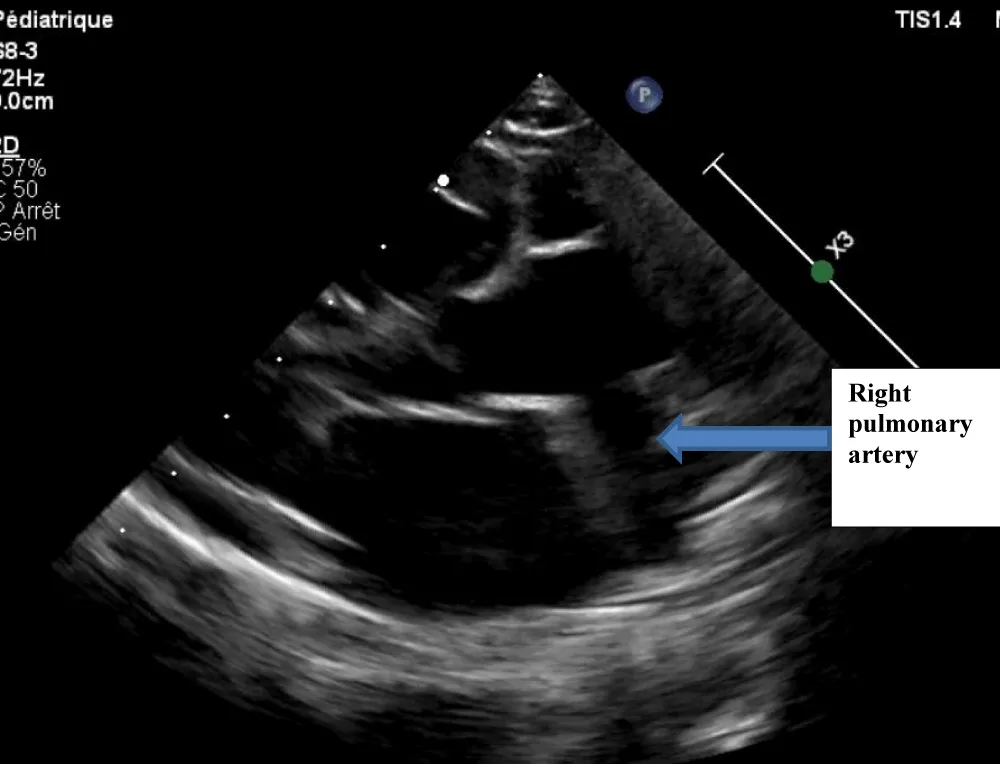

Figure 1: Echocardiography image showing the Right Pulmonary Artery (RPA) exiting the aorta.

The electrocardiogram showed bi-atrial and left ventricular hypertrophy. On frontal telethorax, cardiomegaly with a supra-diaphragmatic peak, a right inferior arch overhang, and peri-hilar vascular overload, predominantly on the right. Cardiac ultrasound revealed a situs solitus heart with levocardia. The aorta normally emerges from the left ventricle, without obstruction. After a few centimeters, it gave way to a right pulmonary artery that filled correctly in systole without obstruction (Figures 1,2). The left pulmonary artery arises directly from the right ventricle. All cardiac cavities are dilated—suprasystemic pulmonary hypertension with ostium secundum-type atrial septal defect with right-to-left shunt. Cardiac angioscan confirmed the diagnosis, showing a 13 mm right pulmonary artery arising from the aorta. The left pulmonary artery arises directly from the right ventricle and measures 9.73 mm, with a functional pulmonary valve (Figures 3,4). Biological tests revealed microcytic hypochromic anemia at 9.3 g/dl. Medical treatment was based on furosemide, captopril, and spironolactone. A surgical cure after catheterization with reimplantation of the right pulmonary artery was indicated. The child died before surgery.